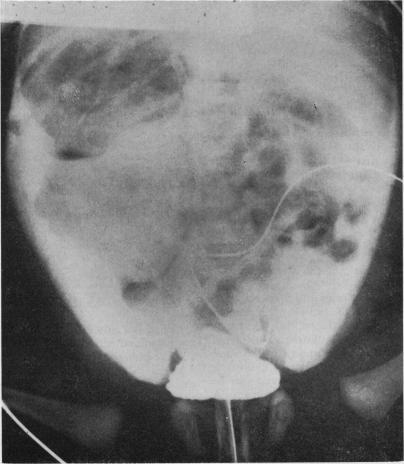

Two premature infants who presented with neonatal ascites due to apparent spontaneous rupture of the bladder are described. In both children the site of bladder rupture was clearly shown, but neither at time of presentation nor at subsequent review at age 7 years and 7 months, respectively, was any other renal tract abnormality detected.